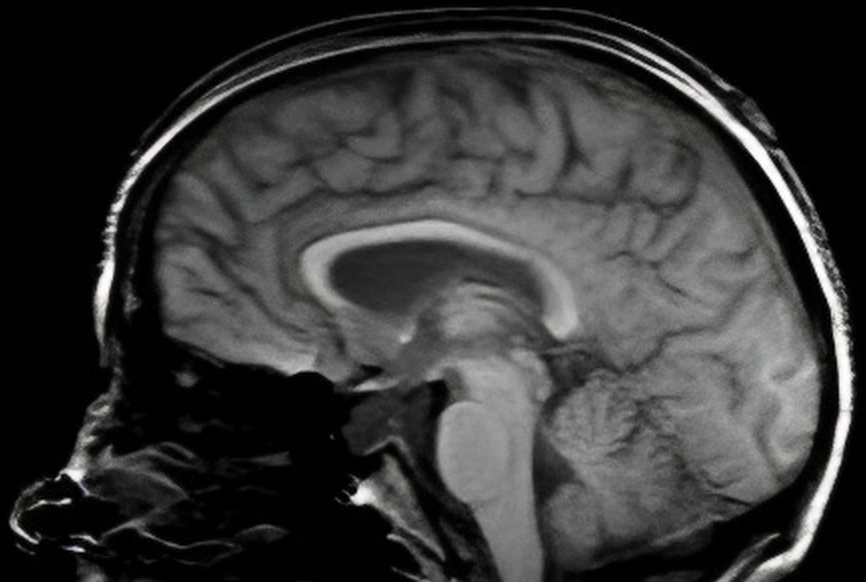

Subarachnoid hemorrhage scan

The Life-Altering Day: My Subarachnoid Hemorrhage

My journey through a life-altering experience with a subarachnoid hemorrhage.